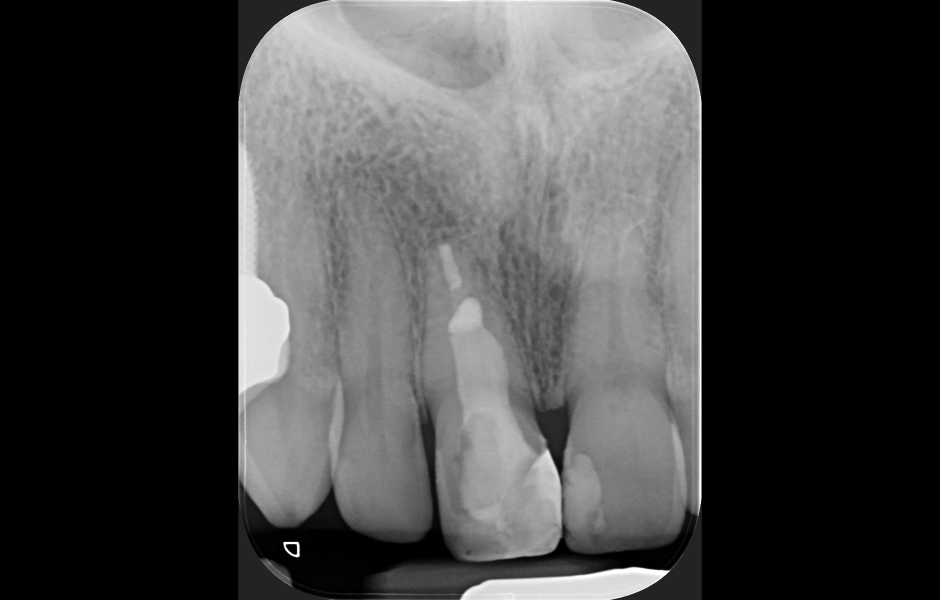

Obr. 4.1: Předoperační snímek horního levého prvního moláru. Oba kanálky mesiobukálního kořene byly kompletně kalcifikované a nebylo možné je ortográdně zprůchodnit.

Obr. 2.1: Předoperační rentgenový snímek horního pravého druhého moláru. Je patrná drobná laterální radiolucence indikující přítomnost laterálního kanálku.